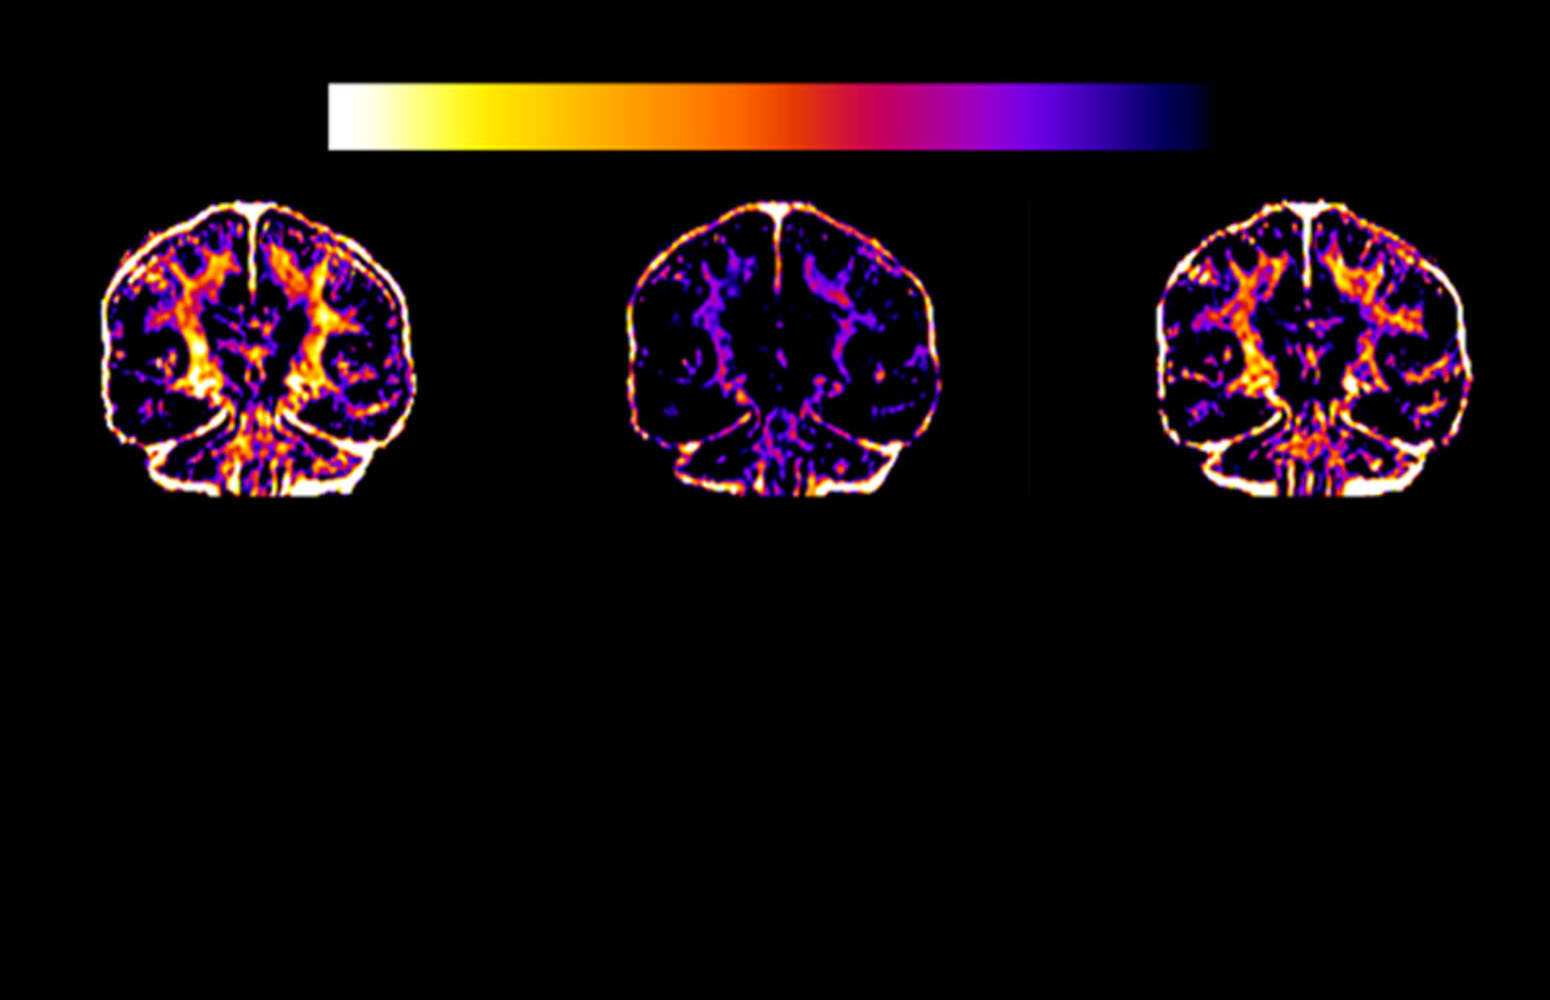

Stem cells have the capacity to divide and differentiate into different types of specialised cells. The UPV/EHU research group has obtained cells very similar to neurons; they “manage to produce electrical impulses like those of neurons by means of the differentiation of stem cells in human dental pulp, the soft tissue located inside the tooth,” they said. The main milestone of this study was “the obtaining of cells that display functional excitability and which synthesise a type of neurotransmitter that regulates neuronal activity, without having been genetically modified; the primary dental cells were simply cultured with differentiation factors and were subjected to precise stimuli to generate cells with neuronal electrophysiological activity”, said the researchers of the Signaling Lab at the UPV/EHU. This had never been achieved before.”

Neurotransmitters are substances released by neurons that can send excitatory or inhibitory signals to make neurons generate an electrical impulse or not. “The cells that we managed to differentiate are capable of synthesising a neurotransmitter known as GABA,” explained the researchers. “It is a type of inhibitory signalling, in other words, it controls whether the neuron that receives it fires electrical impulses or not. And that is very important because there are neurodegenerative diseases such as Huntington's disease or conditions such as epilepsy in which there is a selective death of those types of cells in specific areas of the brain, and a resulting hyper-excitability of the brain circuitry”.